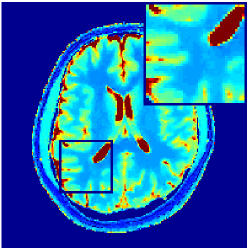

VI-E In-vivo experiments

Two sets of experiments were conducted here: first, we used the 2D and 3D acquisition sequences for scanning a healthy volunteer’s brain (real-world acquisitions). Figures 6 and 7 display the parametric maps reconstructed from 2D spiral and radial readouts. We computed the T1, T2 and proton density (PD) maps using baseline reconstruction algorithms ZF, VS, LR, FLOR, AIR-MRF and our proposed LRTV. While baselines use DM either for quantitative inference or also during reconstruction (i.e. AIR-MRF), we further compare the DM-free LRTV’s performance when cascaded to DM, KM and MRFResnet for quantitative inference. For the 3D spiral acquisitions we compared LRTV and its closest competitor VS in Figure 8. Outcomes from other tested algorithm are displayed in the supplementary materials (Figure S5). Since FLOR does not use dimensionality-reduction, our system ran out of memory during 3D reconstruction; hence results are not reported in this case.

VI-E1 Discussion

The LRTV-DM and LRTV-MRFResnet perform on par, and both outperform all tested baselines for reconstructing T1, T2 and PD maps in all acquisition schemes. This can be observed both visually in Figures 6, 7, 8, S2 and S3, and quantitatively in Table IV across all tested metrics. Other baselines were unable to successfully remove the under-sampling artefacts in TSMIs, and these errors propagated to the parameter inference phase and resulted in inaccurate maps. Temporal-only priors incorporated within LR are shown insufficient to regularise the inverse problem and LR sometimes (e.g. 2D spiral acquisitions) can admit solutions with even stronger artefacts than the model-free ZF baseline. This issue was previously studied for other non-Cartesian MRF readouts that similar to our spiral/radial trajectories, miss to sample the corners of the k-space in all timeframes (see section 2.2.2 and figure 2 in [19]). In the absence of reference for the k-space corners information, the LR iterations despite minimising the objective can converge to solutions with high-frequency artefacts, as visible in the computed maps. This highlights the need for adding an appropriate spatial-domain regularisation. FLOR reduces the LR’s artefacts but this improvement is limited because the suggested nuclear norm penalty does not incorporate an explicit spatial regularisation. Further for reducing artefacts, FLOR can introduce an undesirable bias in the computed T1/T2 maps e.g. see error maps in Figures S2 and S3. The non model-based VS baseline incorporates spatial regularisation and results in spatially smoother maps than ZF and LR, but it is unable to output artefact-free images. Further and consistent with our in-vitro experiment, we observe that VS overestimates the T2 values (e.g. in White and Grey matter regions) in tested 2D acquisitions i.e. the spatial regularisation trades off agains the quantification accuracy. The model-based AIR-MRF adds spatial regularisation through 2D/3D low-pass Gaussian filters however this trades off the sharpness of the computed maps and can increase the errors at the tissue boundaries (we searched Gaussian spreads that keep the blurs and high-frequency artefacts minimal). For our acquisition readouts, Gaussian filters performed better than disk filters of [19] for avoiding strong Gibbs artefacts. On the other hand, the spatiotemporally regularised LRTV greatly improves the TSMI reconstructions i.e. 4 dB enhancement compared to the closest competitor baseline (Table IV). This enables computing accurate and aliased-free multi-parametric inference using DM or the DM-free learning-based alternative MRFResnet as visible in Figures 6, 7, 8, S2 and S3. MRResnet and DM score competitive quantitative inference results i.e. T1 and T2 MAPE less than 5% and 9%, respectively (Table IV). KM also outputs comparably accurate T1 maps, however this shallow learning model despite having a model size larger than MRFResnet, is unable to learn accurate T2/PD quantification and it results in poor estimated maps, consistent with our observations in section VI-C.